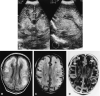

Background and purpose: In the early 1980s, diagnosing periventricular leukomalacia (PVL) in neonates by using cranial sonography was possible for the first time. Our purpose was to investigate the possibility of diagnosing PVL in the acute stage by using MR imaging. We evaluated early MR features of hypoxic-ischemic brain injury in neonates with periventricular densities (flares) on cranial sonograms to determine the added value of MR imaging over sonography alone for early diagnosis of brain damage.

Results: Fifty infants were classified according to the highest sonographic grade up to the day of MR imaging: 23 infants had sonographic grade 1 (flares < 1 week), 15 had sonographic grade 2 (flares > or = 1 week), four had sonographic grade 3 (small localized cysts), and eight had sonographic grade 4 (extensive periventricular cysts); none had sonographic grade 5 (multicystic leukomalacia) on the day of MR imaging. Overall, the additional information provided by MR imaging (over sonography alone) consisted of the depiction of hemorrhagic lesions in 64% of the infants. Extent and severity of the hemorrhages varied from isolated punctate lesions to extensive hemorrhages throughout the white matter; the latter were followed by cystic degeneration at autopsy in two infants. In nine of the 12 infants with cystic PVL, MR images showed more numerous or more extensive cysts. In addition, in two infants, MR images showed cysts not present on sonograms. In 32% of the infants, MR imaging provided no additional information; in these children, all but one had flares on sonograms whereas MR images showed no abnormalities or a zone of mild periventricular signal change.

Conclusion: MR imaging can depict the precise site and extent of hypoxic-ischemic brain injury at an earlier stage and allows a wider differentiation of lesions as compared with sonography alone. Hemorrhagic PVL is considered to be rare, but was present in 64% of our study population.